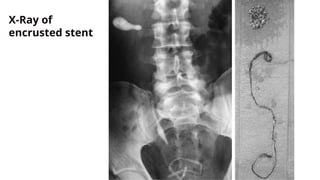

X-Ray of

encrusted

stent

encrusted stent

Aravantinos E, Gravas S, Karatzas AD, Tzortzis V, Melekos M. Forgotten, encrusted ureteral stents:

a challenging problem with an endourologic solution. J Endourol. 2006 Dec;20(12):1045-9.